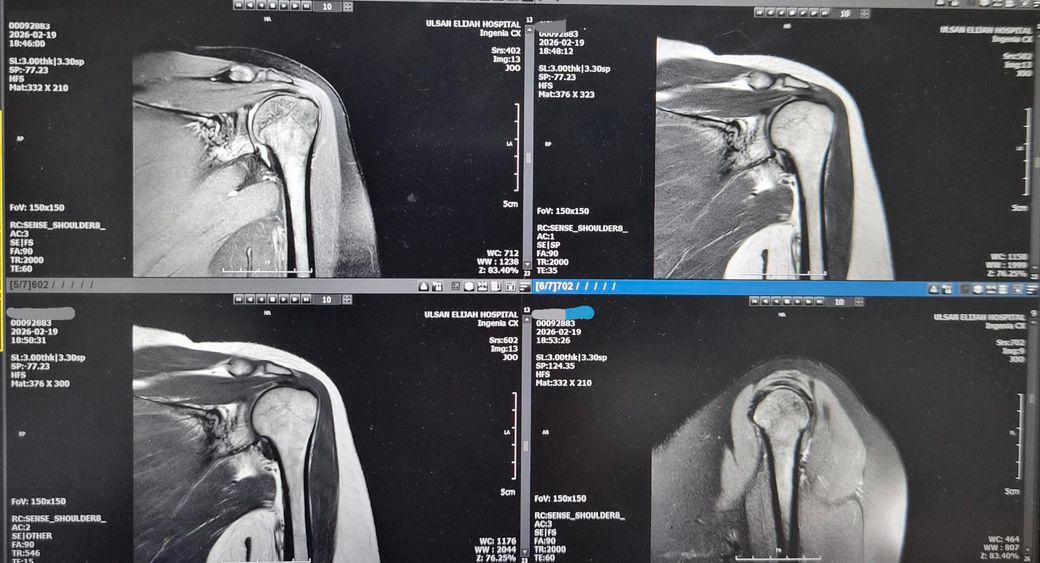

왼쪽어께가 아파서 엑스레이 찍고 MRI저녁에

찍었어요.MRI판독좀 해주세요! 의사소견으로는

골절됬다가 뼈가 붙었다고 했어요. 뼈도좀 튀어나왔죠?그리고

어께충돌증후군이 있다고 치료확인서에 적혀주셨어요. 어께안쪽이 찌릿하고 뭔가 사이에

걸리는 느낌도나요!딱딱 소리도 나구요.

왼쪽어께 통증있어요.앗까는 엑스레이 사진만 올렸었는데 이번에는 MRI같이 올려봐요.

MRI상 "어깨충돌증후군(견봉하 충돌) + 회전근개 자극/염증"이 있어 팔 들 때 걸림·찌릿함·딱딱 소리가 설명됩니다.